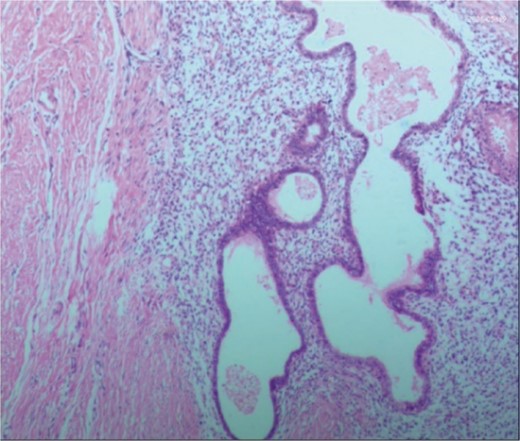

A 38-year-old married female patient presented with a lump near her anus 10 years ago, without apparent cause or symptoms such as redness, swelling, heat, or pain, nor cough, abdominal pain, or diarrhea. No specific treatment was administered. The patient now reports that the lump has grown larger and is accompanied by increasing swelling and discomfort. Seeking further diagnosis and treatment, she visited our outpatient department, where she was admitted with the condition “perianal lump.” Physical examination revealed a body temperature of 36.5°C, pulse rate of 86 beats/min, respiratory rate of 19 beats/min, and a blood pressure of 134/85 mmHg. Admission symptoms include perianal swelling and pain, with itching; no signs of fever, chills, rupture, or pus discharge; bowel movements once or twice daily, and normal urination. The patient has one child and underwent a lateral epidural resection 12 years ago due to natural childbirth. Specialist examination revealed a 4-cm lump with a hard texture at 7–11 o’clock next to the anus, and a radial surgical incision at the 7 o’clock anal margin. Digital rectal examination found no lump, depression, or induration in the anus, and no blood on fingertips. The initial diagnosis was a perianal lump. Auxiliary examinations included ultrasound, which revealed a 4-cm lump in the subcutaneous soft tissue near the anus with minor blood flow signals within and around it, suggestive of an inflammatory lesion (Fig. 1A and B); and pelvic MRI, which suggested a left perianal lump consistent with a perianal abscess (Fig. 2A and B). Under spinal anesthesia, the perianal lump was removed, and postoperative pathology confirmed the presence of endometriosis (Fig. 3).

Postoperative pathology: the endometrial glands have typical stroma, blood, and macrophages containing hemosiderin.